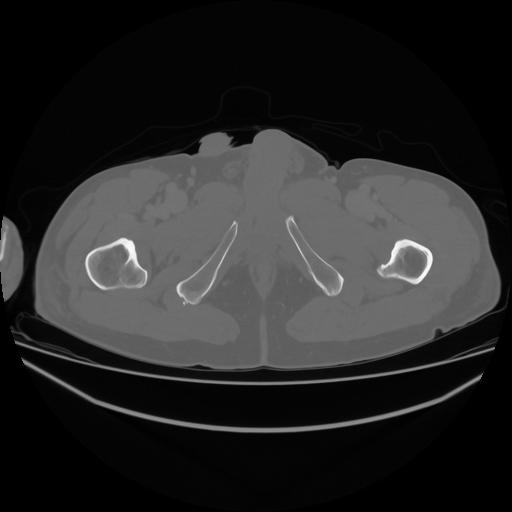

5 CUERPO,CE,Vol,1.0,CUERPO,,